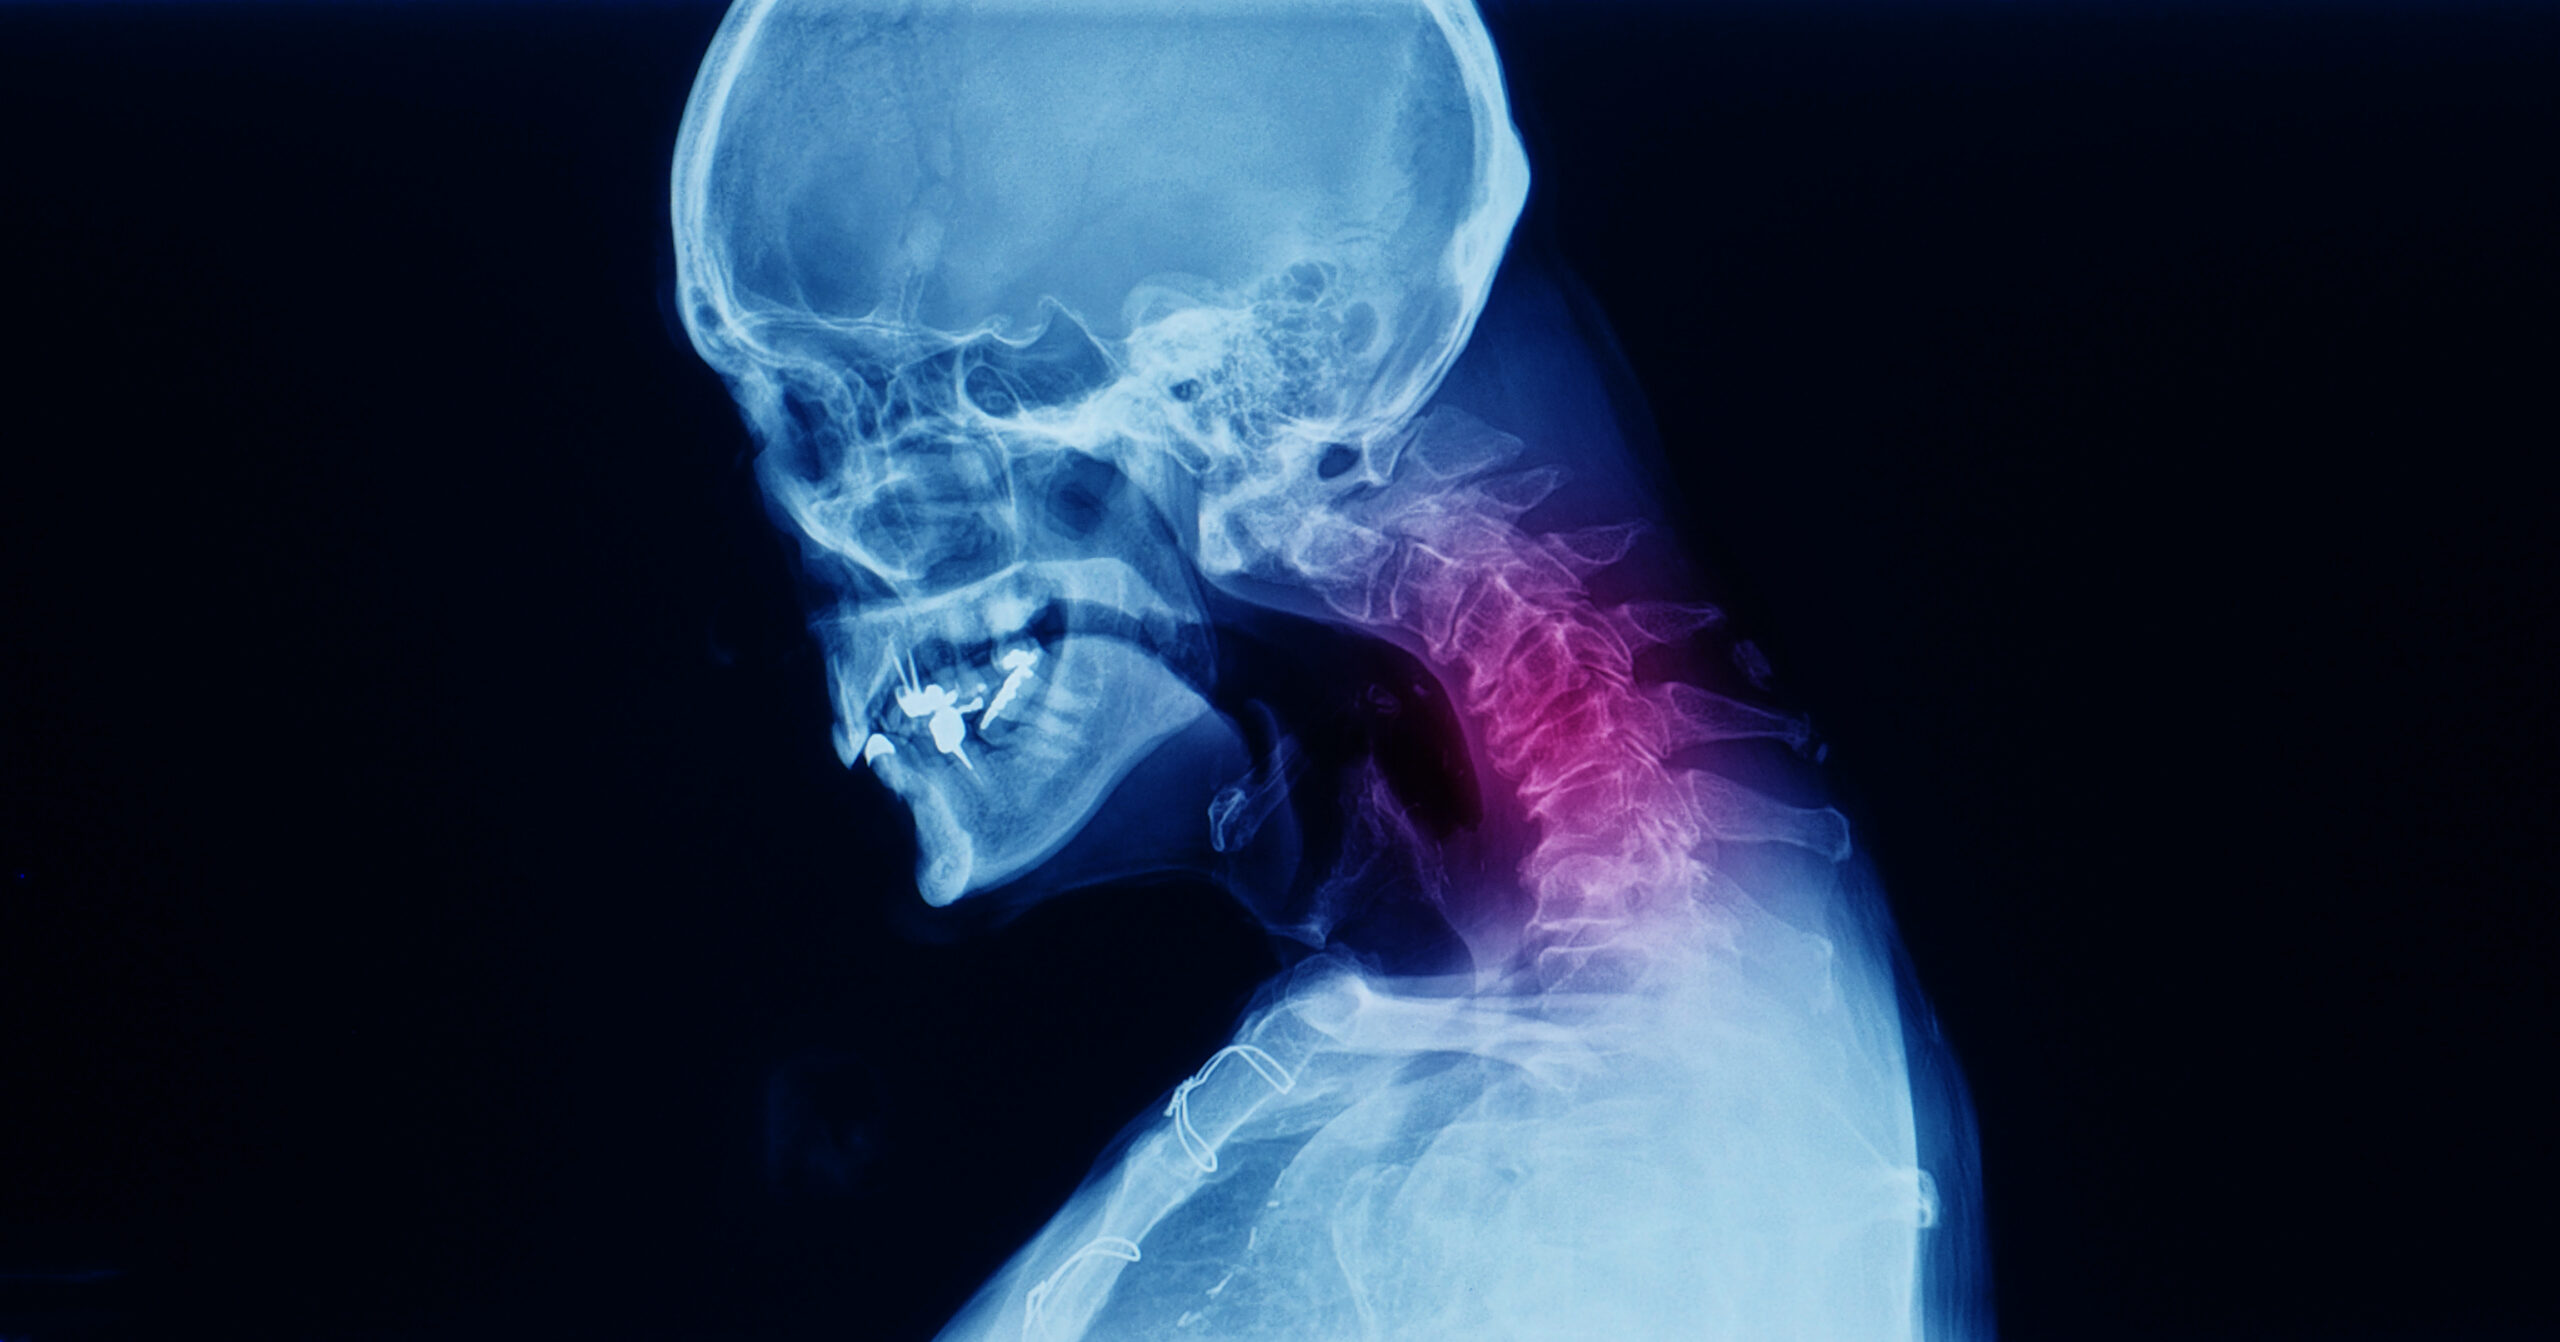

Su médula espinal es un grupo de nervios que se extiende desde su cabeza hasta su espalda baja. La columna cervical es la parte del cuello. La mielopatía cervical espondilótica (MCE) es una compresión de la médula espinal en el cuello. Una compresión de la médula espinal significa presión, pellizcos o aplastamiento sobre ella.

Los cambios en los huesos, discos y ligamentos de la columna vertebral pueden causar presión sobre la médula espinal. A veces, los crecimientos llamados espolones óseos agregan presión a la columna vertebral. Estos cambios a menudo ocurren debido al envejecimiento normal. La artritis de la columna vertebral y el traumatismo de la médula espinal pueden ser otras causas de la MCE.

Su médico le realizará un examen físico y analizará los síntomas. Buscará cambios en sus sensaciones, fuerza y reflejos. Su médico también realizará una prueba de resonancia magnética (IRM). Esto usa ondas de radio para tomar imágenes de su columna vertebral. La prueba puede confirmar si tiene compresión de la médula espinal en el cuello. También puede mostrar otros problemas que tienen síntomas similares a los de la MCE. Es posible que su médico tenga que hacer otras pruebas para confirmar la causa de la MCE. Una de estas pruebas puede ser una tomografía computarizada. También puede derivarlo a un ortopedista o a un neurocirujano.